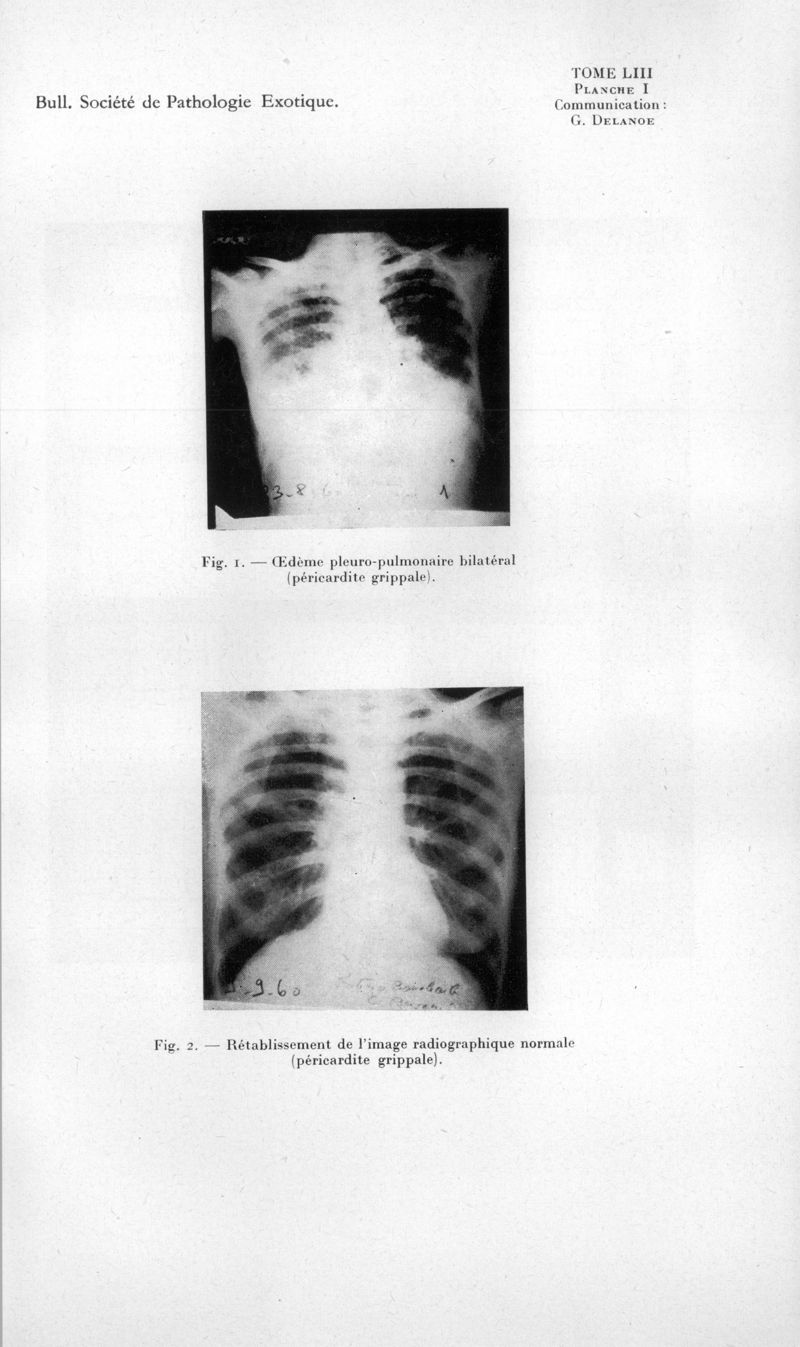

Bulletin de la Société de pathologie exotique et de ses filiales

1960, tome 53. - Paris : Masson, 1960.